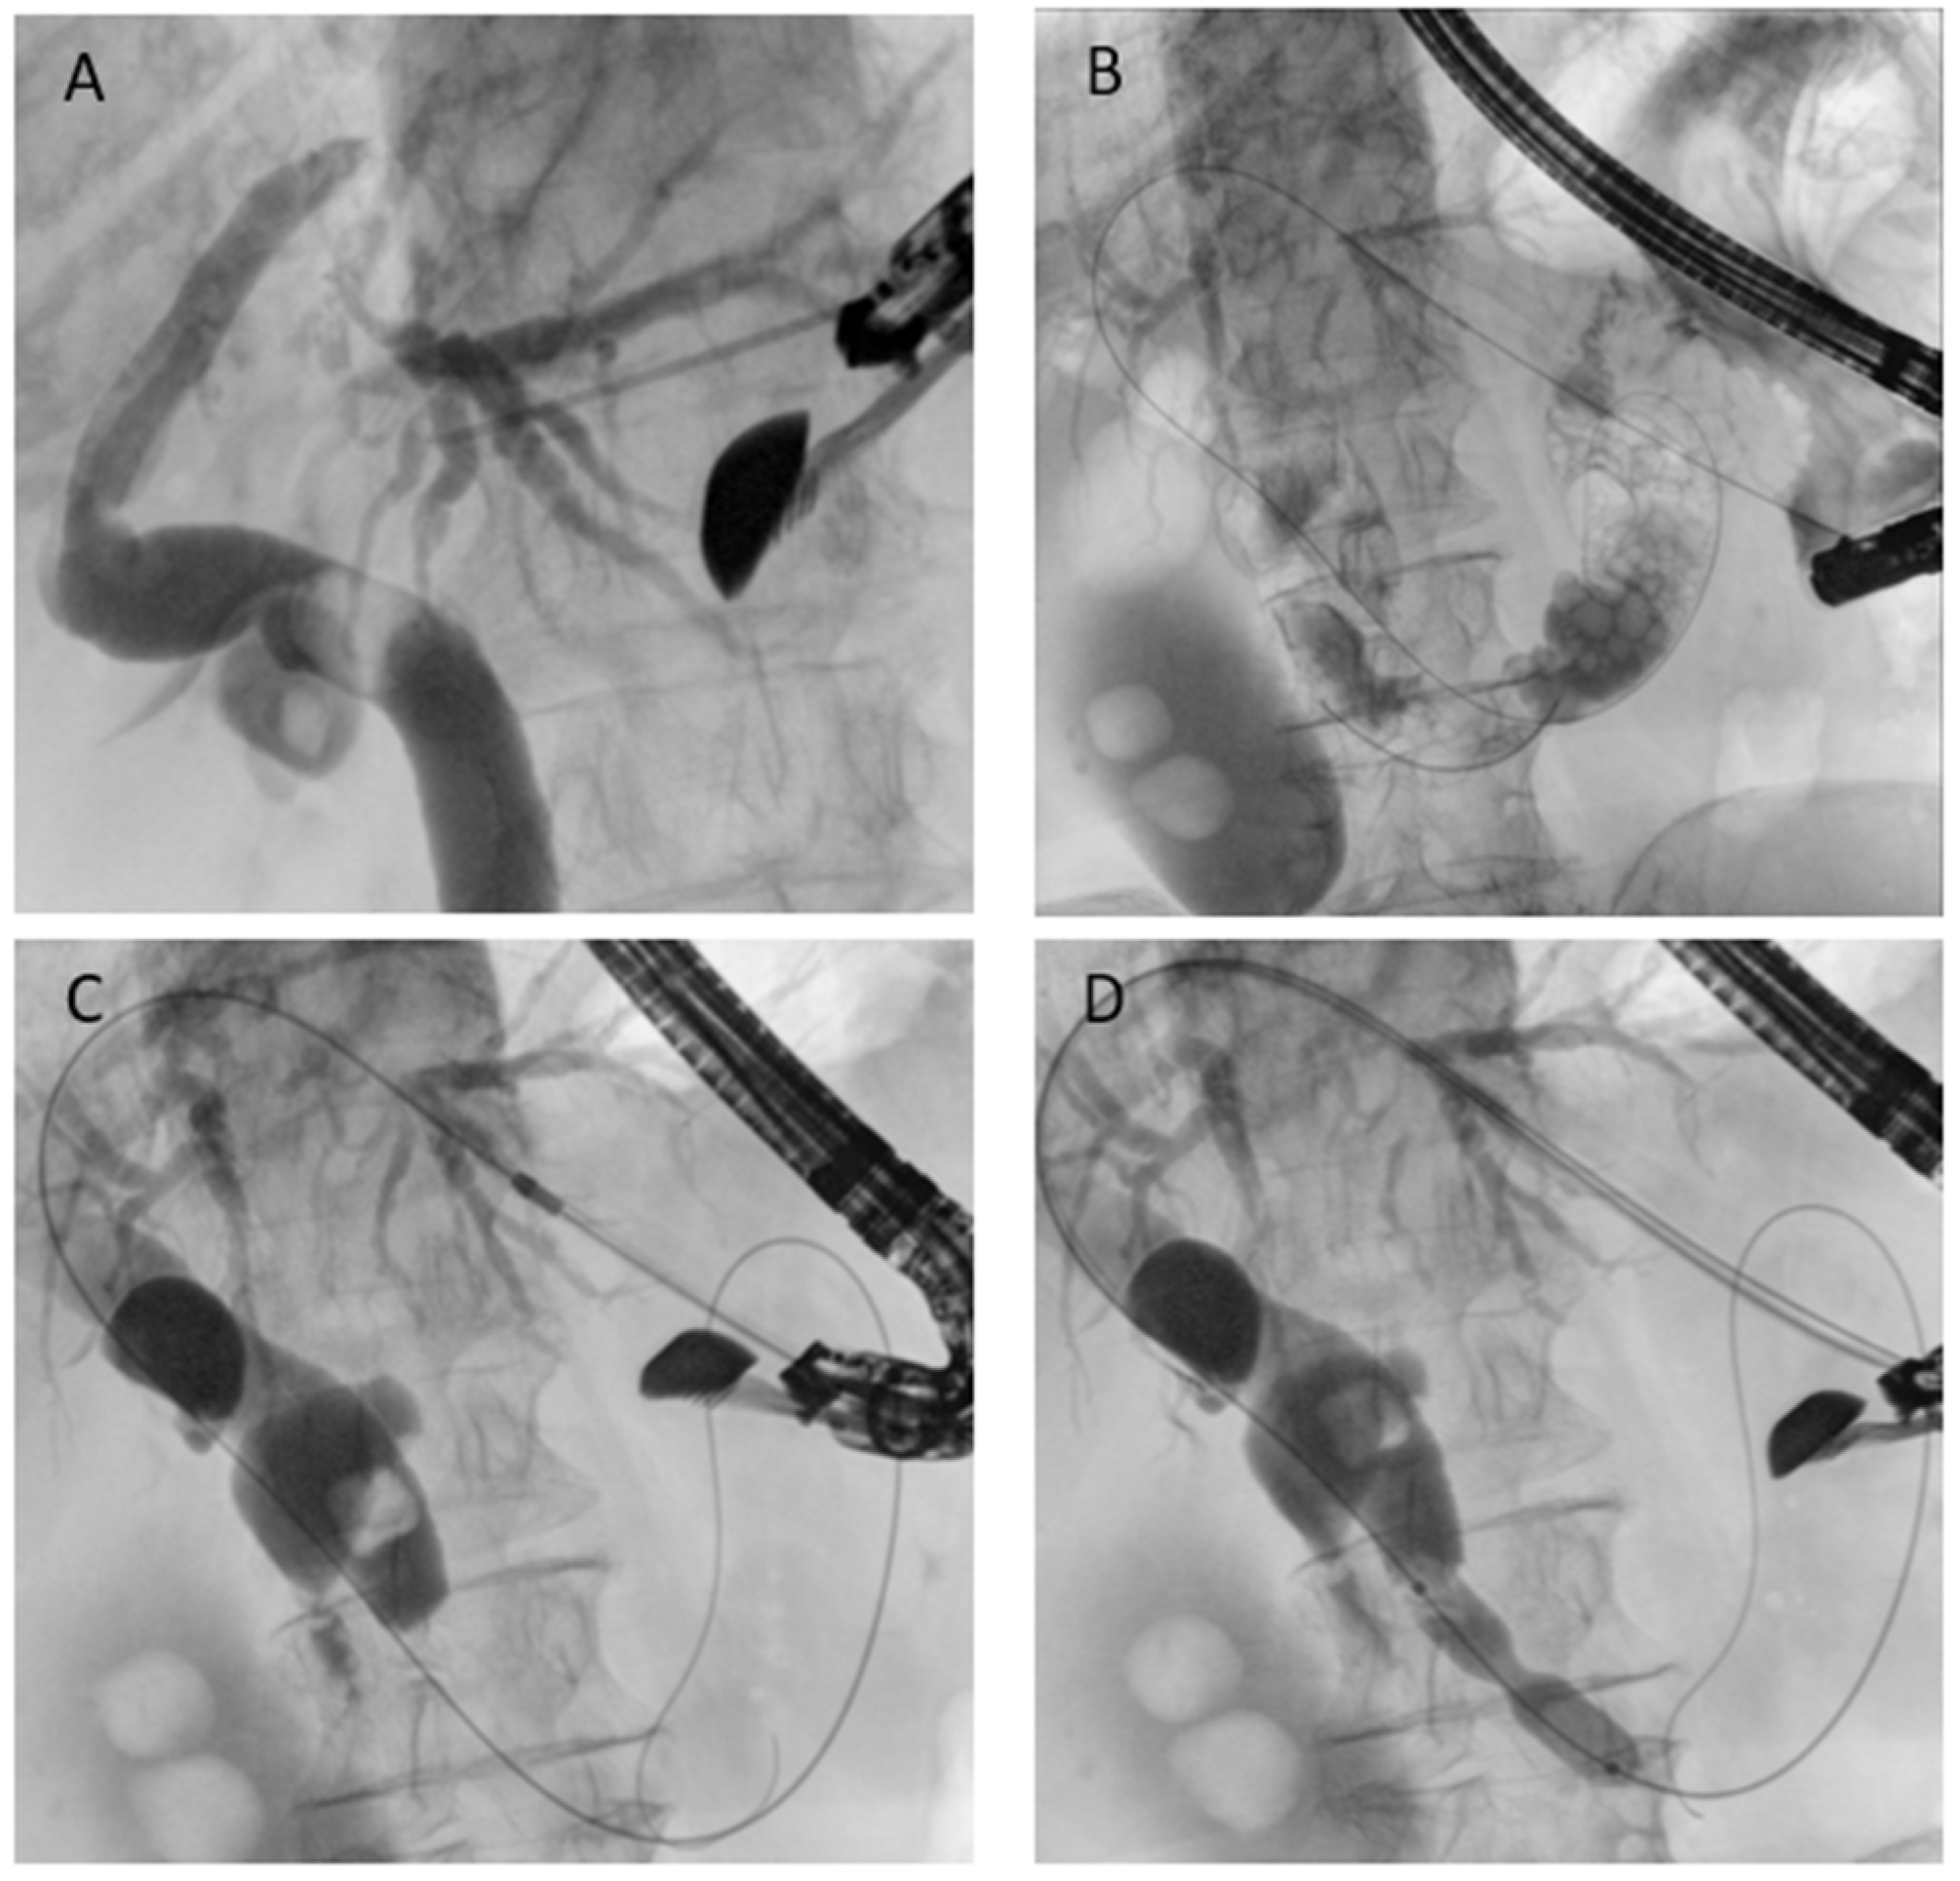

Figure 7. EUS-guided antegrade drainage. (A) Puncture of the intrahepatic duct; (B) guidewire passage into the biliary tree and across the papilla; (C) dilation of the gastric access using a cystotome; (D) endoscopic papillary dilation performed with a biliary balloon dilatation catheter.

5.3.2. EUS-Guided Antegrade Drainage

EUS-guided antegrade drainage is conceptually similar to interventional radiology: the technique involves puncture of a biliary duct, usually from the stomach, using a large caliber needle (usually 19- or 20-Gauge needle), guidewire passage into the biliary tree and, through the papilla/anastomosis, into the downstream bowel (Figure 7). The endoscopist can perform a dilation if necessary and remove biliary stones when present or place a self-expandable metal stent. Technical success rates above 85–90% and clinical success of around 80–90% have been reported. AEs occur in 10–15%, mostly bile leakage or cholangitis [44]. The main advantage of antegrade stenting is that it preserves a physiologic drainage route and avoids external catheters, while the drawback is that reintervention can be technically challenging once the stent is in place. Generally, there is no need to place a stent to protect the initial needle access [45].